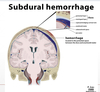

meninges: pia mater (tear/rupturing)

Location of all intracerebral hemorrhages leads to intracranial hemorrhage (aka cerebrovascular accident)